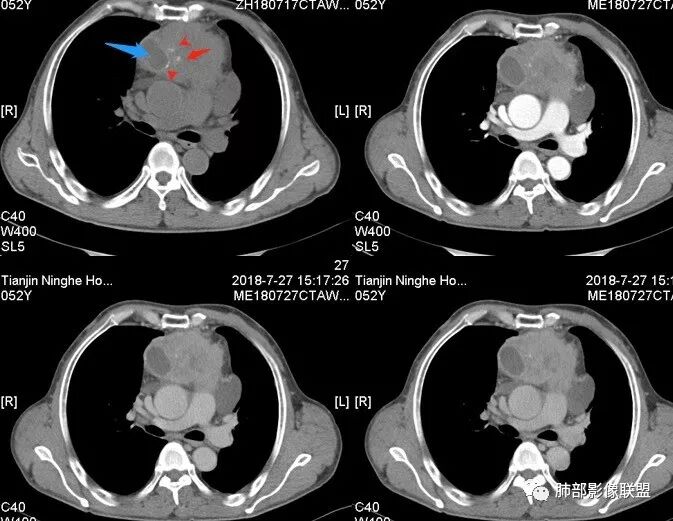

Yiren  Sishui(厶水伊人):上腔静脉受压后移,无侵犯,内乳动脉在其外侧,中心生长,定位纵隔,年龄>30岁,浅分叶,未见明显纤维分隔,其内见微钙化,坏死明显,周围脂肪间隙模糊,心包受累,考虑B3型胸腺瘤或胸腺癌.

大雄:中年男性,发现左前胸壁血管曲张1天入院肿标:细胞角蛋白19片段明显增高,神经元特异性烯醇化酶稍高CT:前纵膈巨大实性占位,边缘膨隆,质地较硬,纵膈脂肪间隙模糊,压迫纵膈大血管(头臂静脉明显狭窄)但未见包绕。平扫可见囊变及钙化,增强中度延迟强化,可见大片不规则坏死区。未见纵隔淋巴结肿大,胸骨骨质破坏及胸水。考虑:恶性肿瘤,胸腺癌可能。

水晶石头 (许建林):患者中年男性,因左前胸壁血管曲张1天就诊。查体左颈前胸壁、左上臂静脉曲张。血管彩超左颈内血静脉流淤滞。肿标:细胞角蛋白19片段明显增高,神经元特异性烯醇化酶稍高胸部CT:前纵隔巨大实性占位,边缘膨隆、清晰,纵隔脂肪间隙模糊,压迫纵隔大血管,未见包绕。平扫可见囊变及钙化,增强中度延迟强化,可见大片不规则坏死区。未见纵隔淋巴结肿大、胸骨骨质破坏及胸水。综合考虑恶性肿瘤,胸腺癌可能性大,鉴别恶性畸胎瘤。

崔少钢:中年男性,左侧颈内静脉、左侧前胸壁及左上臂静脉曲张,提示有静脉阻塞,另患者有恶性家族史。影像:前纵隔占位,有浅分叶,周围脂肪间隙不清晰,且见小淋巴结,内有坏死,上腔静脉受侵,内有钙化,支持胸腺癌。

附近有淋巴结

大肿块,边缘不清,伴随肿大淋巴结,上腔静脉受侵犯——恶性

侵袭性胸腺瘤?胸腺癌?老年,钙化、肿大淋巴结,边缘侵犯、累及心包、侵犯上腔静脉——支持

4.  纵隔淋巴结肿大及纵隔大血管(上腔静脉)受侵犯,提示胸腺癌或类癌。

结合临床表现患者应该存在左无名静脉明显侵犯,可惜未提供相应层面影像资料。

5. 此患者NSE增高,提示神经内分泌肿瘤可能,纵隔神经内分泌癌最常见的是不典型类癌,胸腺类癌临床上可伴相关临床表现。肿瘤体积巨大,边缘清晰,强化显著(与鳞癌不同),肿瘤内边缘规则的管状血管影(鳞癌内血管是破坏、纤细、僵硬);